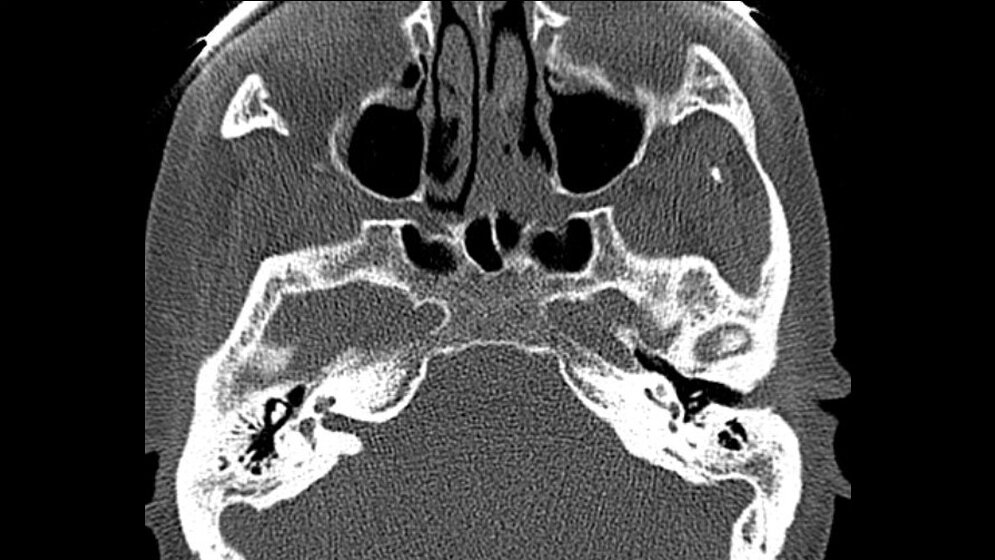

Der Processus mastoideus als Teil des Schläfenbeins zeigt lufthal-tige Zellen mit verschiedenen Varianten. Die Pneumatisation im Bereich der Schädelbasis kann bis okzipital ausgedehnt sein. Es ist eine Normvariante der Pneumatisation des Processus mastoideus.

Processus mastoideus as a part of temporal bone shows cells of pneumatization with several variants. The occipital bone is an accessory site of skull base pneumatization. It is a normal variant of temporal pneumatization.